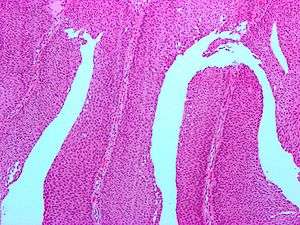

| Micrograph of a PUNLMP. Intermediate magnification. H&E stain. | |

Histologically, they have a papillary architecture with slender fibrovascular cores and rare basal mitoses. The papillae rarely fuse and uncommonly branch. Cytologically, they have uniform nuclear enlargement.